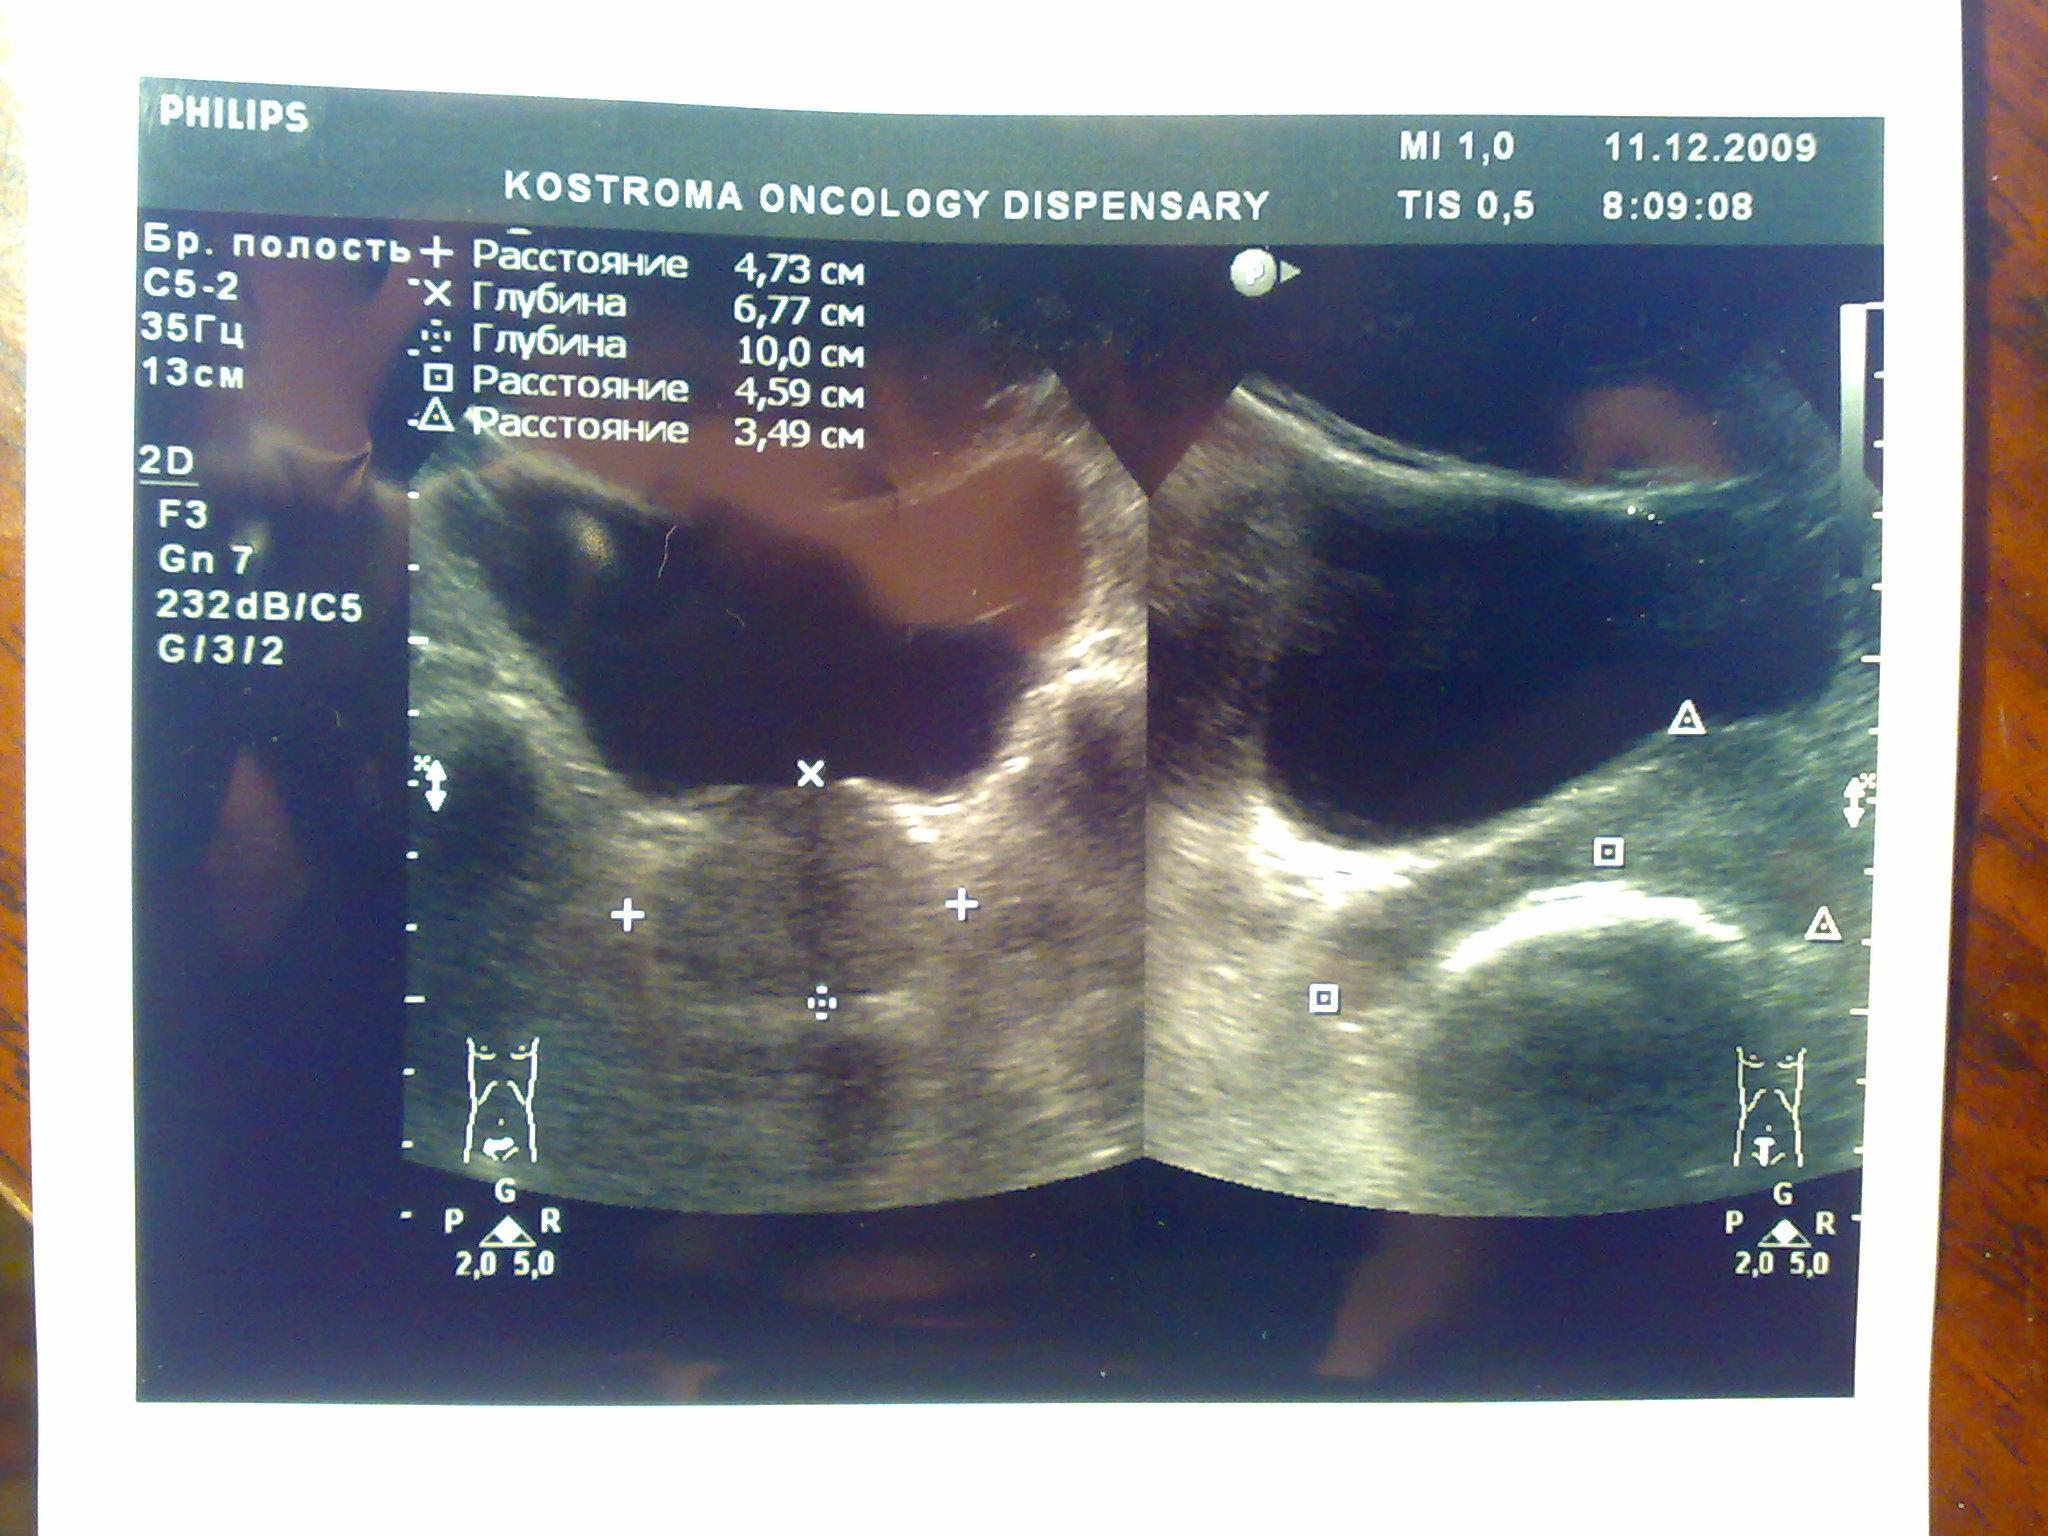

Доброго времени суток. В начале декабря сходил в банное заведение, употребил там пиво, вечером был сексуальный контакт с постоянной партнершей, на утро у обоих появилось жжение при мочеиспускании, у меня покраснение губок полового члена, умеренные выделения прозрачные, анализы крови и мочи в норме, ПЦР у обоих отрицательные. У девушки соэ 28, лейкоциты в моче выше 200, у меня все в норме, бак посев отделяемого из уретры выявил обильный рост Ешерихии коли, принимал внутремышечно Цефотаксим по 1г 2раза в день в течении 5 дней, во время лечения появилось жжение и дискомфорт в промежности. Трузи показало увеличение простаты, расширенные семенные пузырьки около 3 мм, кальцинатов и инфильтратов нет, в область мочевого пузыря не вдается, остаточное количество мочи около 10 мл, кол лейкоцитов в отделяемом из уретры 5-8 в поле зрения. Сейчас принимаю по назначению уролога Нолицин 400 мг по таблетке два раза в день, Палин 250 мг по 1 два раза и азитромицин 250 по одной раз в сутки, свечи на ночь Простатилен курс на 10 дней, уже прошло восемь массажей улучшение незначительное, симптомы в обшей картине сохраняются, железа со слов уролога стала более упругой и меньших размеров. У меня стала страдать эрекция, полной уже нет около 2 месяцев. После эякуляции хочется мочится, неприятные скребущиеся ощущения в промежности, сперма раньше выстреливала, а сейчас вытекает, выстреливает только первая порция, появились боли в мошонке слева, особенно после массажа, подскажите пожалуйста что делать, как лечится, какие еще анализы сдавать. Прикреплены снимки узи.Заранее благодарен.